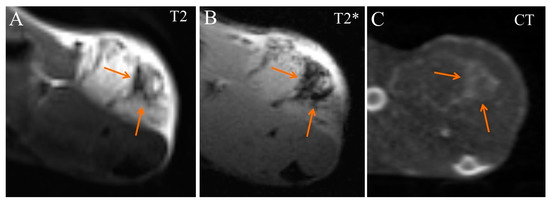

2. Results